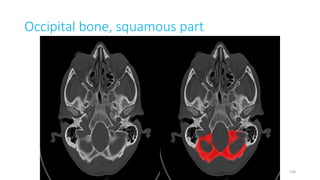

Occipital bone (squamous part)

Occipital bone (squamous portion)

Occipital bone, squamous part